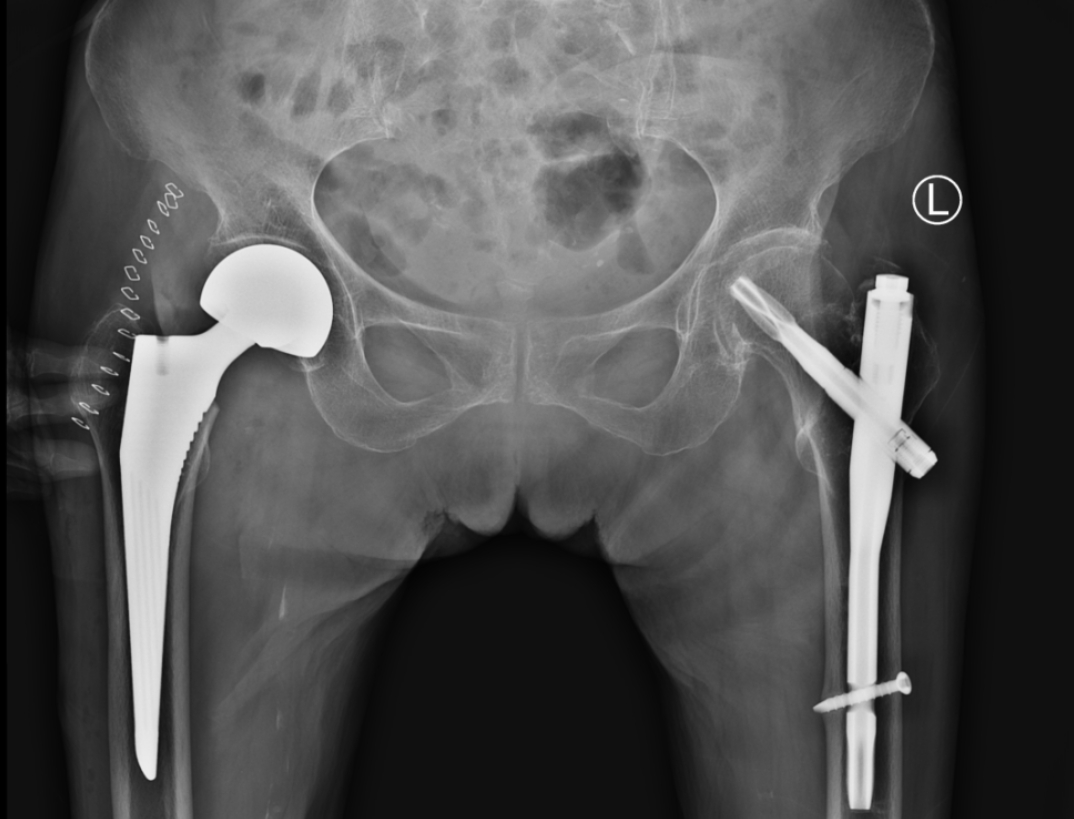

随后入住关节外科,积极完善相关检查,廖中亚院长分析了患者的身体情况,并与患者家属沟通,精心制定最佳治疗方案,为帮助石奶奶尽快下床、行走,避免骨折带来的并发症,决定实施“右侧人工股骨头置换术”。同是髋部骨折,老年人的股骨颈骨折治疗不同于转子间骨折,股骨颈骨折后采用人工股骨头置换术可帮助患者尽早康复,且避免股骨头坏死以及不良并发症的发生。

术前

术后

入院第二天,在手术麻醉科团队的配合下,廖中亚主任医师带领团队为其快速、成功实施了“右侧人工股骨头置换术”。术后患者疼痛缓解,术后第二天,在护士及家属的陪护下,石奶奶就已经可以下地走路。